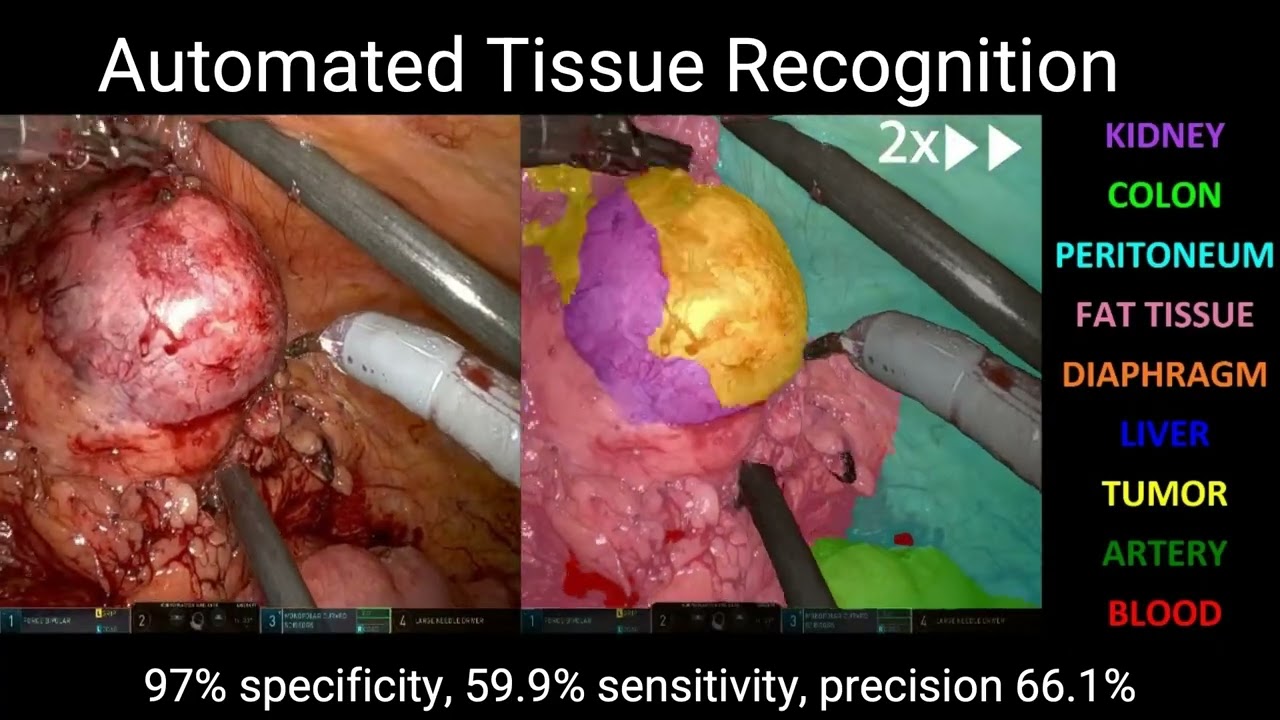

Surgical Scene Segmentation